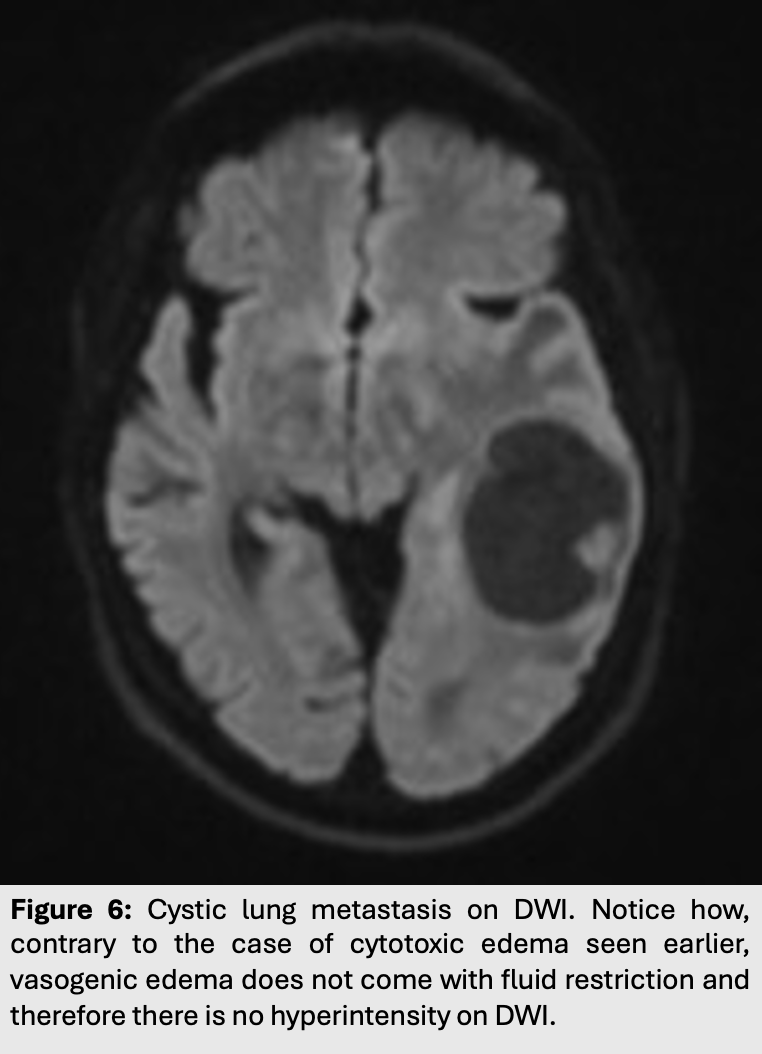

Figure 1: Right MCA stroke on T1. Red arrow illustrating blood flow disruption and territory ischemic infarct.

This type of edema is most commonly seen in strokes or ischemic syndromes.